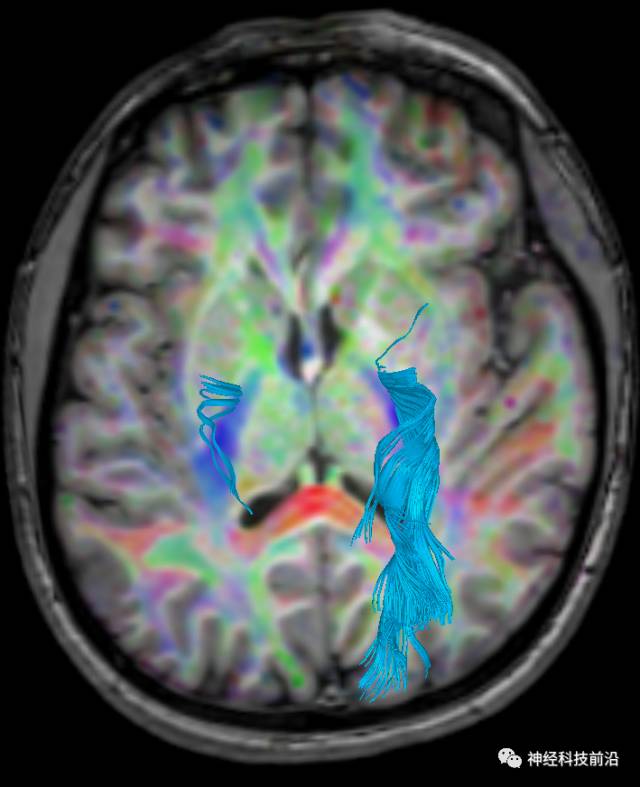

DTI原始图像与T1融合图像

下面为皮质脊髓束的走形及位置